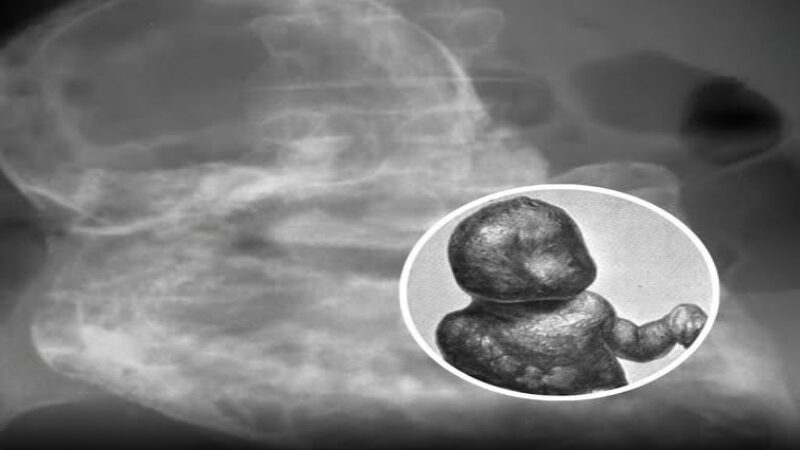

মহিলাটি জানতেন না যে তিনি কখনো গর্ভবতী ছিলেন, অথচ চার দশক ধরে তার শরীরে একটি মৃত ভ্রূণ ক্যালসিফায়েড অবস্থায় জমে ছিল। এই বিরল অবস্থা ‘লিথোপেডিয়ন’ নামে পরিচিত। এটি ঘটে যখন ভ্রূণ একটি পেটের গর্ভধারণে মারা যায় এবং দেহ তাকে শোষণ করতে অক্ষম হয়। সংক্রমণ থেকে নিজেকে রক্ষা করার জন্য দেহ ভ্রূণটিকে পাথরের মতো কঠিন করে তোলে। চিকিৎসা ইতিহাসে এরকম কেস ৪০০-এর কমই রেকর্ড করা হয়েছে।

মহিলাটি তার আগের জীবনে কোনো স্ক্যান বা বড় ধরনের স্বাস্থ্য পরীক্ষা করাননি। পেটের নীচের অংশে দীর্ঘমেয়াদি অস্বস্তি অনুভব করার পর চিকিৎসকেরা ইমেজিং করালে পেলেন একটি কঠিন ভর, যা ভ্রূণের বাঁকা অবস্থার মতো।

পরবর্তী সার্জারিতে নিশ্চিত হলো স্ক্যানের ফলাফল: সম্পূর্ণ ক্যালসিফায়েড ভ্রূণ, যার মৃত্যু দ্বিতীয় ত্রৈমাসিকে ঘটেছিল প্রায় ৪০ বছর আগে। এত বছর ধরে এটি চুপচাপ মহিলার গর্ভে ছিল এবং বড় কোনো সমস্যা সৃষ্টি করেনি।